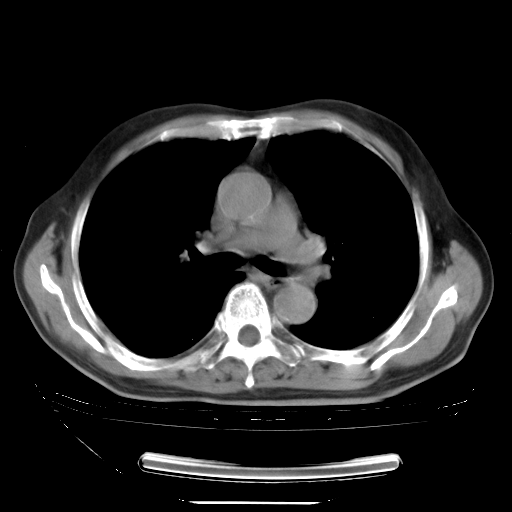

今天复查肺部CT,发现双肺广泛磨玻璃样改变。所以我把3月19日和5月9日相隔50天的肺部CT上传。请大家会诊。

5月9日肺部CT(在4月27日齐鲁医院肺部CT描述部分肺组织磨玻璃样改变,12天后肺组织广泛磨玻璃样改变)

2009年5月9日肺部CT